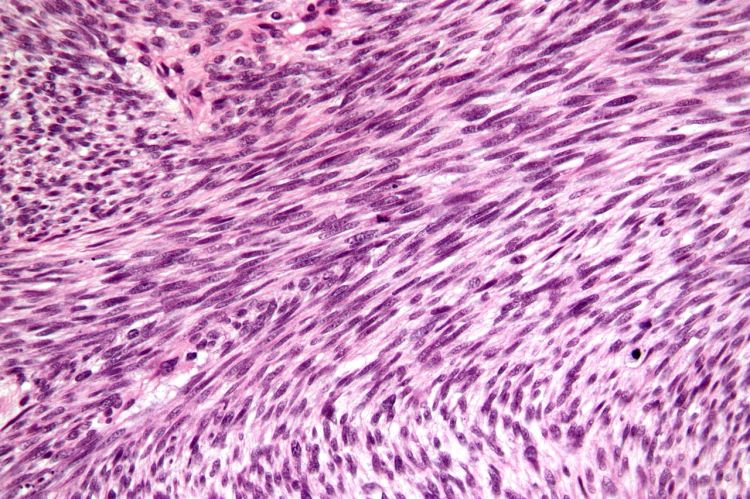

A diagnosis is made by identify the tumor with advanced imaging (usually MRI) and/or obtaining a biopsy of abnormal tissue for histopathology. Other imaging tests such as chest radiographs and an abdominal ultrasound may be recommended to look for spread of the tumor.